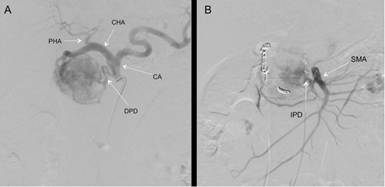

In order to increase patient safety during surgery, an arterial diagnostic and therapeutic angiography was elected. Angiography showed the extreme hypervascularization of the lesion (Figure 2a). The tumor was supplied by the anterior and posterior branches of the superior pancreaticoduodenal arteries and the dorsal pancreatic artery. It was noticeable that the gastroduodenal artery was large in diameter, larger than the common hepatic artery. A “steal like syndrome” due to the hypervascularization of the lesion resulted in the enlargement of the gastroduodenal artery with the resultant of reduced size of the right and left hepatic arteries. The dorsal pancreatic artery was approached selectively through the superior mesenteric artery and embolized with coils along side with the main superior pancreaticoduodenal artery. The tumor blood supply was still maintained by a small branch of the posterior pancreaticoduodenal artery (Figure 2b).

|

Figure 2. a. Transarterial selective angiography of the celiac axis, showing a hypervascular lesion of the head of the pancreas supplied by the posterior and anterior branches of the superior pancreaticoduodenal, the dorsal pancreaticoduodenal (DPD), and a small branch of the inferior pancreaticoduodenal (IPD). Of note is the large size of the gastroduodenal artery relatively to the proper hepatic artery (PHA) caused by “steal like syndrome”. b. The superior and inferior pancreaticoduodenal branches were selectively embolized with coils. CA: celiac axis; CHA: common hepatic artery; SMA: superior mesenteric artery |

Preoperative angioembolization of hypervascular tumors is well documented for renal cell carcinoma [3, 4, 5], spinal tumors and osseous renal cell carcinoma metastasis [6, 7, 8, 9, 10, 11, 12]. This strategy was proven safe and may result in decrease risk of bleeding during surgery and increase operative safety. Preoperative angioembolization for liver metastasis of PNET was previously described [13]. Preoperative embolization of primary pancreatic cancer was rarely described in the English literature. Hirose et al. reported a giant tumor safely resected after preoperative angioembolization [14]. Preoperative angioembolization of the hepatic artery prior to en block celiac axis resection for pancreatic body cancer was also reported [15]. We describe preoperative angioembolization of an extremely hypervascular PNET of the head of the pancreas that lead to a “steal like syndrome” of the hepatic artery. Of note are the hypervascularity of the tumor and the size of its arterial supply in comparison to the hepatic arteries (Figure 2a). The multiple arterial supplies were safely embolized and followed by bloodless surgery and good recovery.